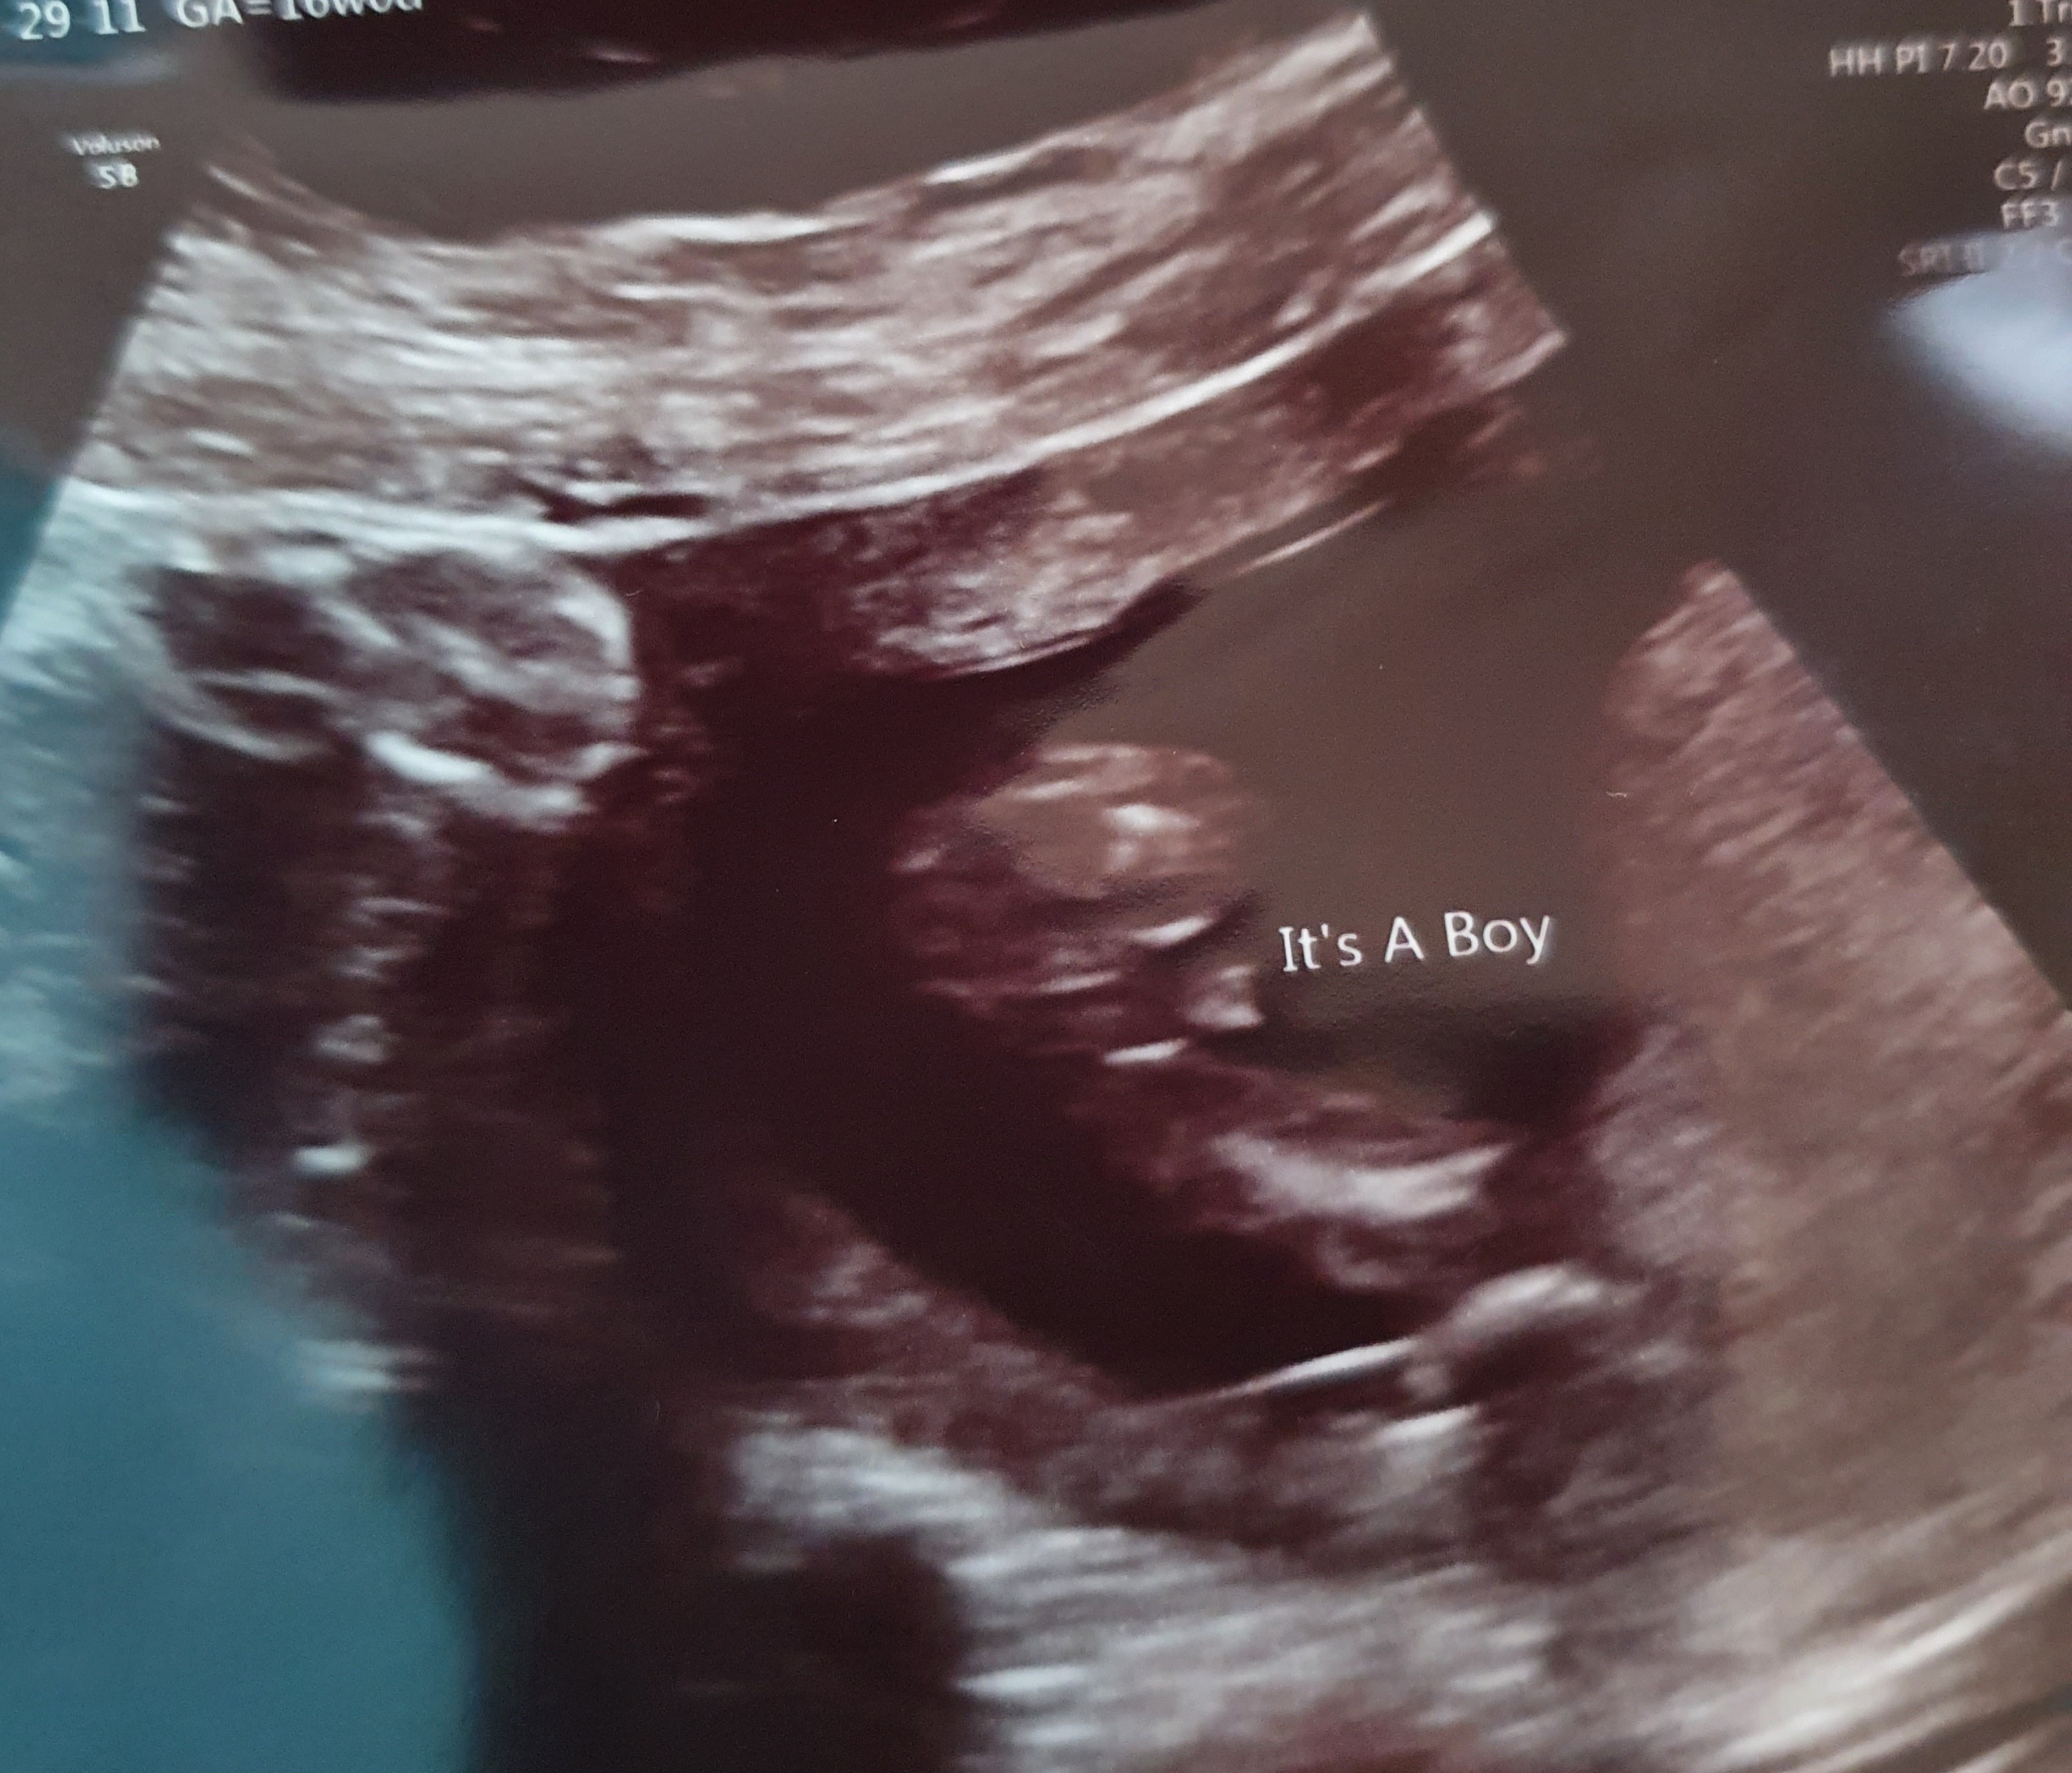

Could you please tell me what you think the gender is? I have 2 boys already, think I might be having my 3rd

Just had gender scan and was confirmed as a little boy........just the potty shot looks a bit different to me? Could you ladies just have a wee look before I buy blue, the guy doing the scan said boy before even looking underneath.Attachment 42805